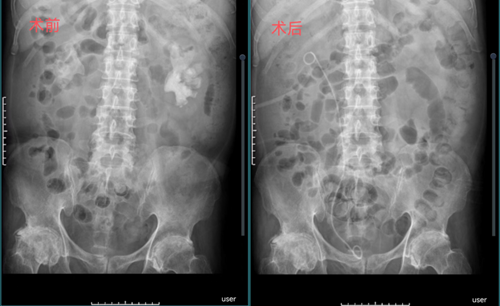

通过围手术期凝血因子替代治疗、术中采取特殊体位,术前术后监测凝血因子等综合措施,在王金根、贾灵华两位主刀医师及麻醉科、手术室全体医护人员的努力下,先后双侧经皮肾镜取石术进展顺利,术后康复顺利,无明显出血、发热等并发症。术后复查腹部平片和CT提示结石彻底清除干净,术后患者血尿、腰疼等不适症状消失,黄先生带着灿烂的笑容出院。